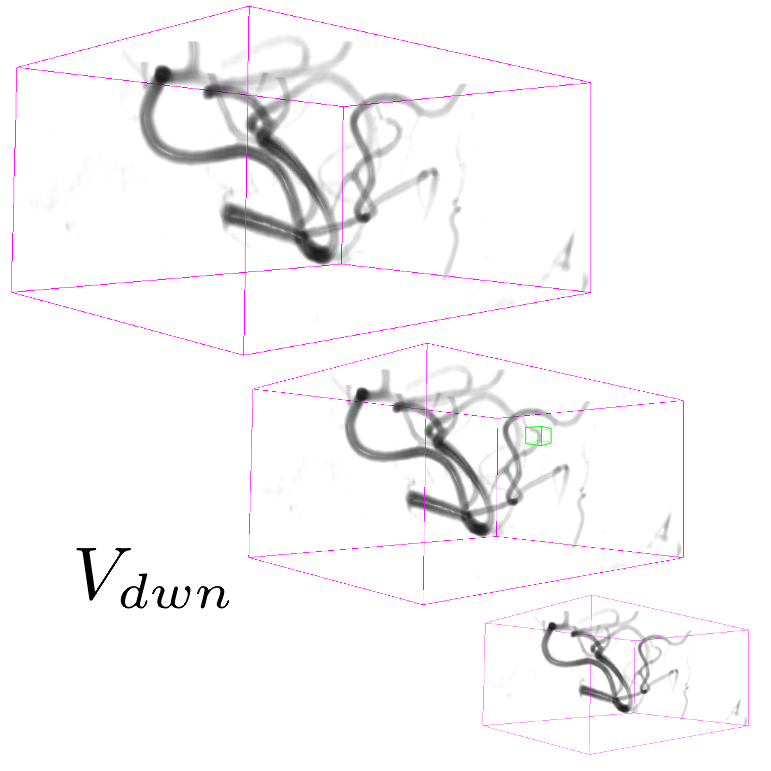

A 3D hand-crafted tortuous and convoluted phantom (HCP) is designed to account for complex vessel patterns, i.e. branching, kissing vessels, scale and shape variations induced by pathologies. Also a set of 20 synthetic vascular trees (SVT) ( voxels) were generated using VascuSynth [10] considering two levels of additional noise (N1: + Shadows: 1 + SaltPepper: ; N2: + Shadows: 1 + SaltPepper: ). Together with the synthetic data, a cerebral Phase Contrast MRI (PC) ( mm), a cerebral Time of Flight MRI (TOF) ( mm) and a carotid CTA ( mm) were used. Vascular network ground-truths (GT) are given in the form of connected raster centerlines for all the synthetic images and for both TOF and CTA.

3.2 Connected Geodesic Paths as Vascular Tree

Representative examples of degraded synthetic images from SVT and the respective GT are shown in fig. 4 together with the connected graphs extracted by VTrails. Analogously, the same set of images are reported for the real images TOF and CTA in fig. 4. Qualitatively, the extracted set of connected geodesic paths shows remarkable matching with the provided GT in all cases. First, we verify the acyclic nature of the graph. We found no cycles, degenerate graphs and unconnected nodes, meaning that the extracted connected geodesic paths represent a connected geodesic tree. Precision and recall are then evaluated for the identified branches. Also, error distances are determined as the connected tree’s binary distance map evaluated at GT. Average errors () precision and recall are reported (meanSD) in table 1. Note that no pruning of any spurious branches is performed in the analysis.

We presented VTrails, a novel connectivity-oriented method for vascular image analysis. The proposed method has the advantage of introducing the SLoGS filterbank, which simultaneously synthesizes a connected vesselness map and the associated tensor field in the same mathematically coherent framework. Interestingly, recent works [17, 9] are exploring Riemannian manifolds of tensors for high-order vascular metrics, however the coherent definition of a tensor field is not trivial for an arbitrary scalar image, as its topology cannot be generally approximated simply by an ellipsoid model [14]. The steerability property of SLoGS stands out as key feature for i. reducing the dimensionality of the kernels parameters in 3D, ii. determining the filterbank’s rotation-invariance and iii. optimizing the 3D filtering complexity in the OLA. Also, the combined rotation- and curvature-invariance of the filtering process results in branch-points that coincide with the locally integrated center of mass of the multiple SLoGS filter responses. This explains the strong response in the CVM at the branch-point in fig. 3. Regarding the acyclic connectivity paradigm employed in VTrails, we experimentally verified that the resulting set of connected geodesic paths forms a tree. The assumption of a vascular tree provides a natural and anatomically valid constraint for 3D vascular images, with few rare exceptions, such as the complete circle of Willis [5]. It is important to note that the proposed algorithm can include extra anatomical constraints to correct for locations where the vascular topology is not acyclic or where noise it too high. Note that despite the optimal formulation of the anisotropic front propagation, a limitation of the greedy acyclic connectivity paradigm is the possibility of miss-connecting branches, potentially disrupting the topology of the vascular network. Overall, promising results have been reported from this early validation, with a fully-automatic extraction configuration. Missing branches occur in correspondence of small vessels, where the effect of degradation is predominant: tiny terminal vessels completely occluded by the corrupting shadows will not automatically produce seeds, hence cannot be recovered under such configuration. Globally, values are comparable to the evaluation tolerance , suggesting that the connected geodesic paths extracted by VTrails lie in the close neighbourhood of the vessels’ centerlines. Moreover, the reported values are comparable regardless the level of degradation. Future developments will address the optimization of the CVM integration strategy in section 2.1 to account for an equalized response over the vascular spatial frequency-bands. Also, the topological analysis of vascular networks on a population of subjects will be investigated in future works to better embed priors in the acyclic connectivity paradigm.